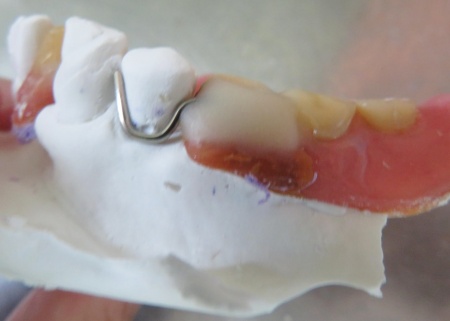

外側のクラスプの位置を確認しました